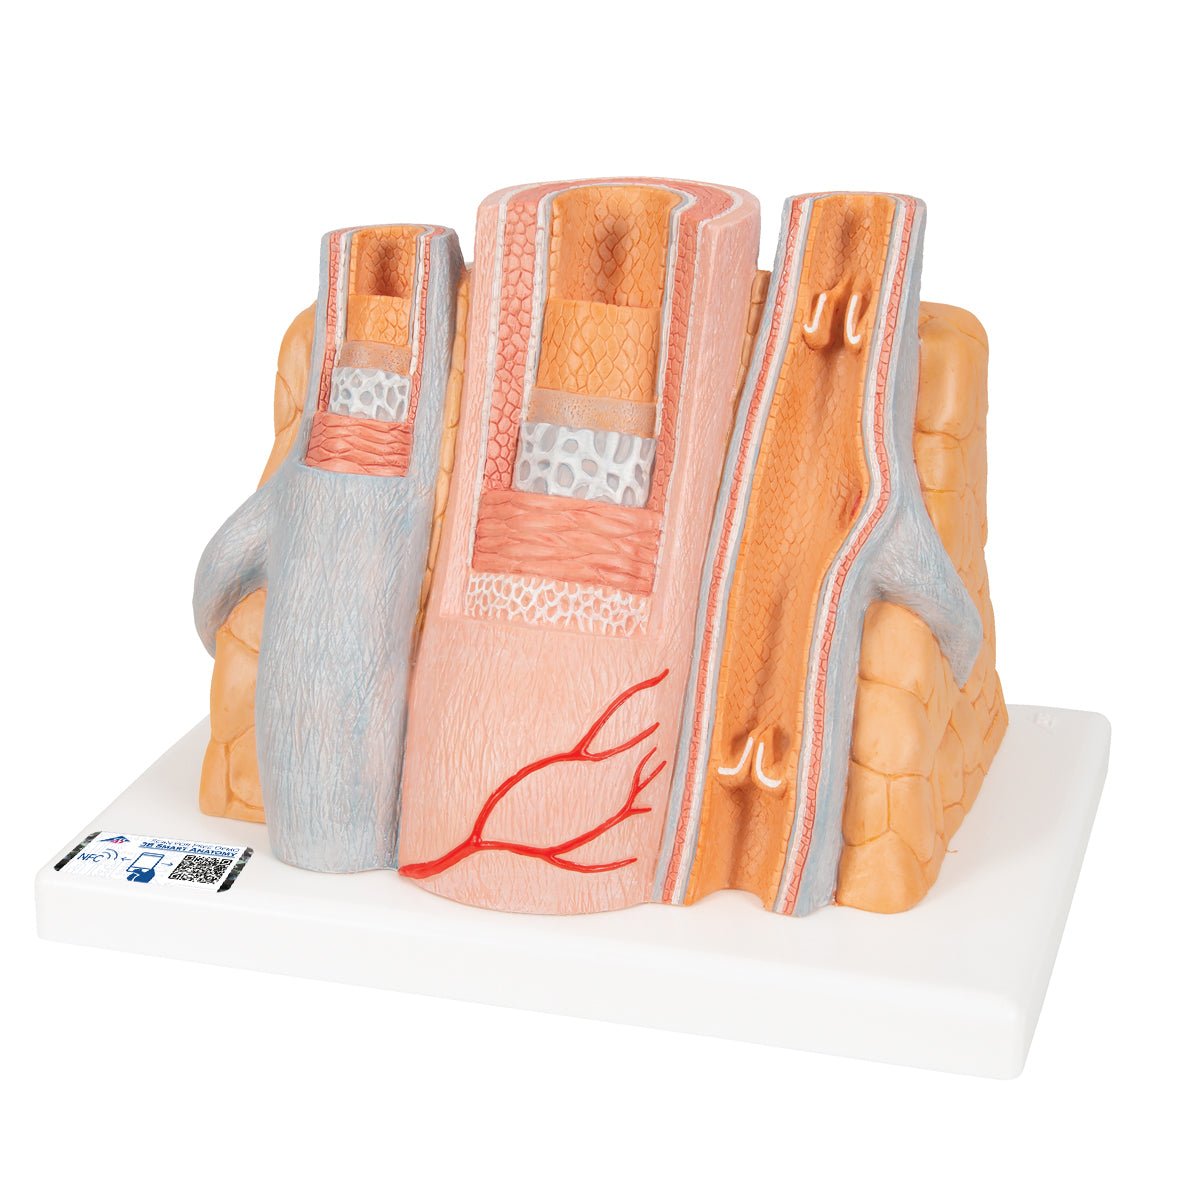

Salg af anatomiske modeller er det bærende element i eAnatomi, selvom vi også bruger mange ressourcer på at udvikle vores egne anatomiske materialer som fx plakater. Anatomiske modeller anvendes til forskellige formål og kan både vise afgrænset væv, organer samt organsystemer. Søger du en simpel model af knoglevæv eller måske en avanceret torso-model baseret på MRI teknologi, kan du finde det hele på eanatomi.com.